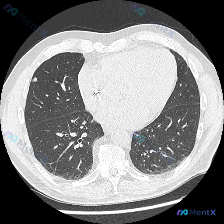

整理了一份胸部CT读片病例,CT层面位于主动脉弓水平,肺窗显示双肺广泛弥漫分布的1-2mm大小的微小结节,分布相对均匀,结节为实性密度,双肺透亮度轻度下降,胸膜和骨质未见明显异常。 现在抛出两个问题讨论: 1. 这个异常影像最准确的术语描述是什么?题干给出的选项是Airspace opacity(气...

看到这个影像分析病例,感觉对大家读片会很有帮助,整理一下思路和大家分享。 病例影像基础信息 这是一份胸部CT肺窗横断面影像,层面位于胸廓上部主动脉弓水平,图像清晰度好,无明显伪影,符合读片要求。 核心影像异常 最开始提问说异常是"Airspace opacity(气腔实变)",但仔细读片分析后发现,...

整理了一份影像读片讨论材料,核心问题是:这个胸部CT肺窗横断面,原提问认为异常是「空气腔隙浑浊(肺实变)」,但实际读片下来,核心异常是弥漫性分布的边界相对清晰的粟粒样小结节,分布广泛覆盖双肺上野,大小均一,没有看到明显的大片实变影、空洞或纤维条索。 这份病例值得讨论的点: 1. 为什么一开始说的「肺...